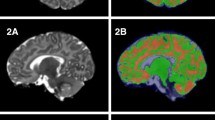

Overview of the image processing and volume calculation pipeline. Upon acquisition and inspection of T1- and T2-weighted images, non-parenchyma tissue is removed and images are aligned to the study-specific template. Subcortical gray matter and white matter atlas priors are then inverse warped to the infant native space and regional volumes are computed

Axial and coronal views of the study specific structural T1- and T2-weighted templates are shown in Fig. 2. Coregistered atlas priors used in subsequent analyses from the structural (Shi et al. 2011) and white matter (Oishi et al. 2011) neonate brain atlases are also displayed in Fig. 2. All successfully acquired individual images were registered to these templates using symmetric diffeomorphic registration with ANTs (Avants et al. 2011a). Representative individual T1- and T2-weighted images aligned in the template space are displayed in Fig. 3. Superimposition of the atlas priors to the infant data was quantitatively assessed by computing percent volume differences, Jaccard similarity and Dice coefficient (Supplementary Table 1). Across all brain regions, the average percent volume difference, Jaccard similarity, and Dice coefficient between the original atlas priors and the infant atlas priors was 0.72, 88.31, and 93.75%, respectively. Total gray matter volume was observed to be the most discrepant brain region, with an average percent volume difference, Jaccard similarity, and Dice coefficient of 2.04, 90.06, and 81.94%. Right middle cingulate gyrus had the smallest percent volume difference (0.24%), while total brain volume had the largest Jaccard similarity (98.52%) and Dice coefficient (99.25%). Overall, these results qualitatively and quantitatively demonstrate the ability of the symmetric diffeomorphic registration to provide accurate alignment between the 1-month brain to the study-specific template space.

Top row: representative axial and coronal views of the study-specific T1-weighted and T2-weighted templates generated from 1-month-old infant brain data. Middle row: subcortical gray matter and bottom row: white matter regions used for volumetric measurement. Regions are overlaid on the T1-weighted template and separated by color

Individual T1- and T2-weighted images aligned to the study specific template space, with subcortical gray and white matter priors overlaid on the individual’s T1-weighted image. Subcortical gray matter and white matter regions are color-coded as in Fig. 2. These representative images demonstrate the ability of the symmetric diffeomorphic registration to successfully map T1- and T2-weighted images to the study-specific template space, while quantitative assessment of overlap shows evidence for good agreement between atlas and individual priors (Supplementary Table 1)